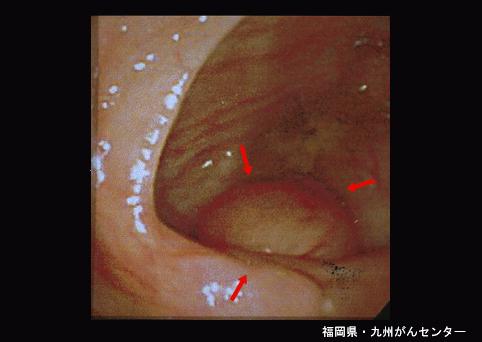

症例提示(所在地,施設名等): 福岡県・ 九州がんセンター

疾患(病理主体)の分類その他の腫瘍/良性虫垂粘液瘤腫

部位(臓器別)大腸/虫垂

検査方法内視鏡

病変の最大径(ミリ)40以上